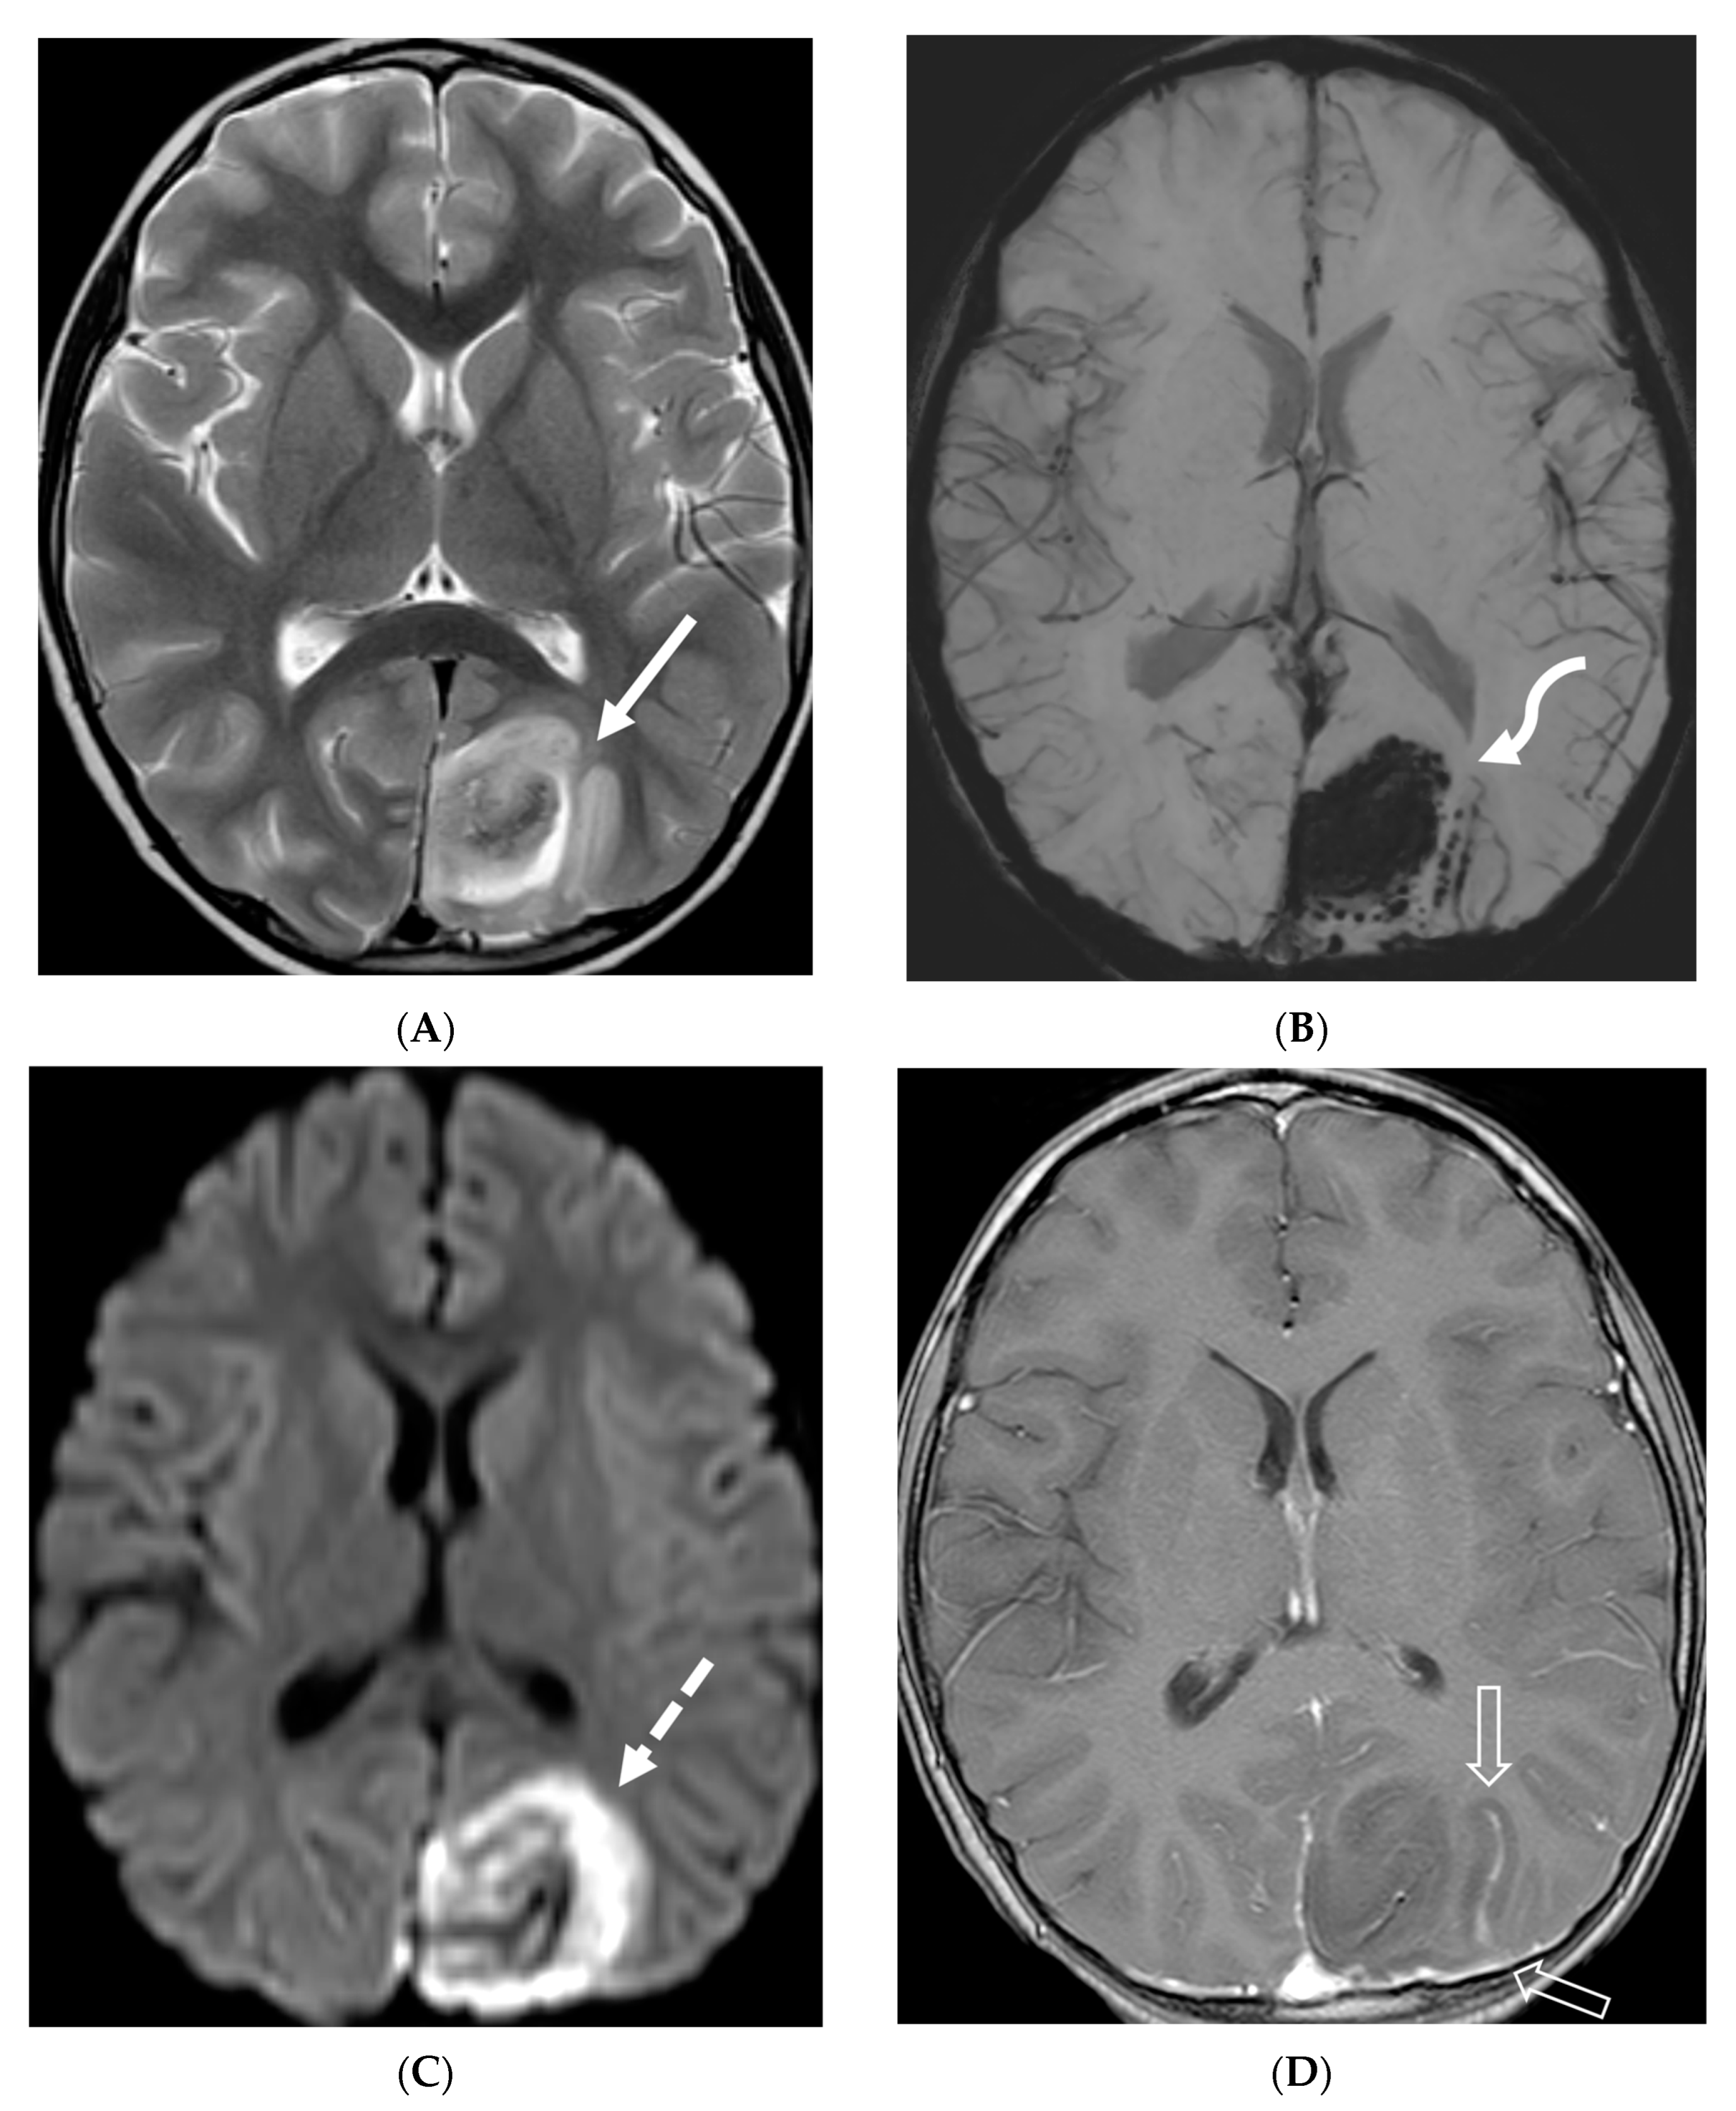

LME has been shown to present early in the disease course and is much more common in children (33%) compared to adults (8%) [107]. Gadde et al. found that 8% of pediatric MOG antibody-associated demyelination cases had only LME without any other central nervous system manifestation. LME when present can be particularly helpful in differentiating from NMOSD [106]. Furthermore, Valencia-Sanchez et al. reported a significant association between LME and cerebral cortical encephalitis in MOG antibody-associated disease. This finding suggests that LME may be an important marker for cortical involvement and potentially more severe disease (Figure 21) [108].

Figure 21.

Sagittal T2 (A,B), axial FLAIR (C), axial T2 cervical spine (D) at the level of C7 vertebral body and Axial T2 orbits (E): 12-year-old girl presented with right focal motor seizure and left temporal lobe slowing on electroencephalogram (EEG). Right eye vision loss and irritability. Ill-defined areas of signal abnormalities are identified within the RIGHT mesial temporal lobe and bilateral medulla (white arrows). FLAIR hyperintensity is identified on the left central sulcus (black arrow). Small focus of signal abnormality is seen on the right side of the cord at the 7th cervical vertebra (C7) (dashed arrow). There is also bilateral papilledema (arrowheads). Post contrast axial T1 (F,G), axial T1 orbits (H) and axial T1 cervical spine at C7 (I): Asymmetric LME (black arrows) predominantly involving the left cerebral hemisphere, with minimal right parietal involvement is seen. Ill-defined enhancement in the right mesial temporal lobe, and right greater than left medulla (white arrows) corresponds to the signal abnormality. There is right greater than left, optic nerve enhancement (curved arrow). Single small enhancing lesion in the spinal cord on the right at the level of C7 corresponds to the signal abnormality (dashed arrow). Features favor a demyelinating process. MOG antibodies were positive at 1:20 in keeping with Myelin oligodendrocyte glycoprotein (MOG) antibody disease (MOGAD).